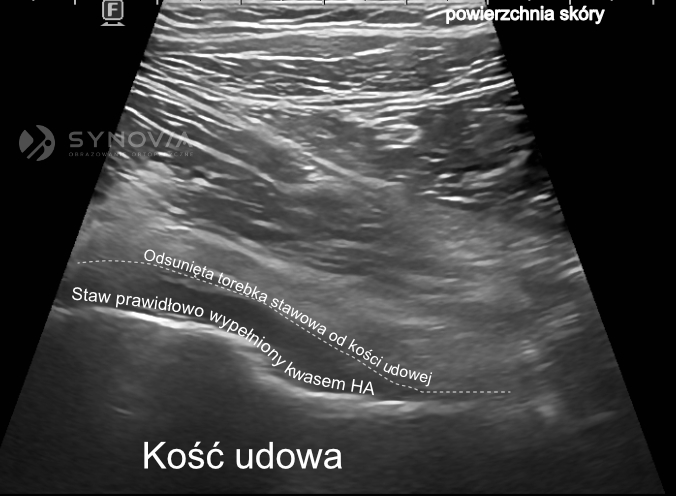

Iniekcje kwasu hialuronowego do stawu, zwane wiskosuplementacją, mają na celu przywrócenie prawidłowych właściwości płynu stawowego. Terapia działa na kilku poziomach:

- Uzupełnienie niedoboru naturalnego HA w płynie stawowym – zwiększenie stężenia kwasu hialuronowego poprawia lepkość i sprężystość płynu, co przekłada się na lepszą ochronę chrząstki.

- Poprawa właściwości lepkosprężystych płynu – dzięki lepszemu „smarowaniu” powierzchni stawowych zmniejsza się tarcie podczas ruchu, co redukuje ból i poprawia komfort poruszania się.

Precyzyjne umieszczenie preparatu w jamie stawowej ma kluczowe znaczenie dla efektu terapeutycznego. Preparat musi trafić dokładnie do wnętrza stawu, aby mógł wypełnić swoją funkcję.